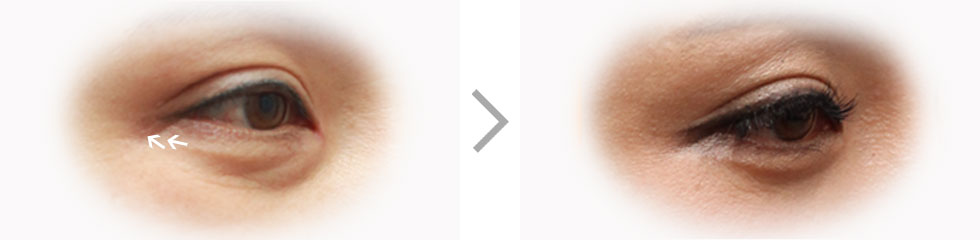

年老后由于老化的现象,皮肤失去弹力,眼皮变得松弛。

这样的眼皮妨碍视野,也造成皱眉,皱额头等,使整个面部看起来年老。

根据皮肤下垂程度或个人状态不同,施行上眼睑或眉毛提升手术,

下眼睑手术等,解决中年人的眼角问题。 重

眉毛提升手术是在眉毛的上侧或下侧开口,提拉下垂的眼皮和肌肉的手术。

不想改变原有的双眼皮线条,或想要改善自然下垂的上眼皮,露出被遮盖的双眼皮时,是非常适用的手术方法。

上年纪后上眼皮和眼角慢慢下垂,给人疲倦的印象。 上眼睑整形手术是切除下垂的眼皮的松弛皮肤,做一个新的双眼皮,

针对妨碍视野扩大和眼角乱纹的问题,一次性解决的手术方法。

上年纪后,不只是上眼皮,下眼皮也会变得下垂,突起。

这种眼睛不只是单纯的去除脂肪,要用再排置,角膜强化等方法来保持弹力和矫正。

眼下皱纹 一点式提升术是通过眼角细微的切口,将松弛的眼袋皱纹和肌肉由一点向上提拉的手术。

切口小,无疤痕顾虑,保留本人原有的眼型,强化眼台,拥有似做非做的柔和有弹力的眼型。